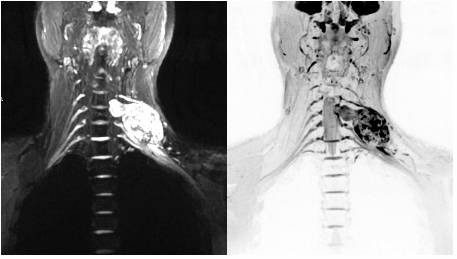

病例

术前检查